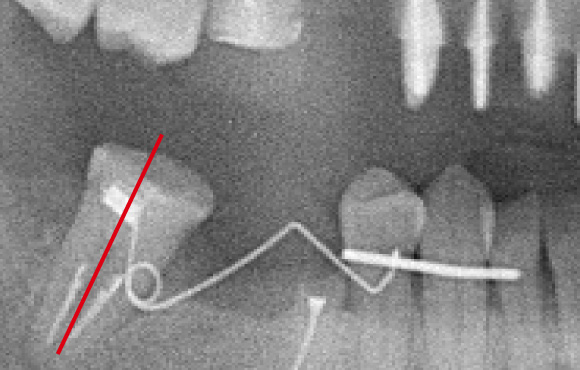

倒れている歯を起こす(アップライト)

手前の歯を喪失したあと、長い間放置したため手前に歯牙が傾いてしまっています。

歯牙を4か月から6か月かけて起こすことができました。

矯正用インプラントアンカー

矯正用のインプラント小さいインプラントから動かしたい歯を引っ張り移動させることも可能です。

移動が終了したら、このインプラントは除去します。